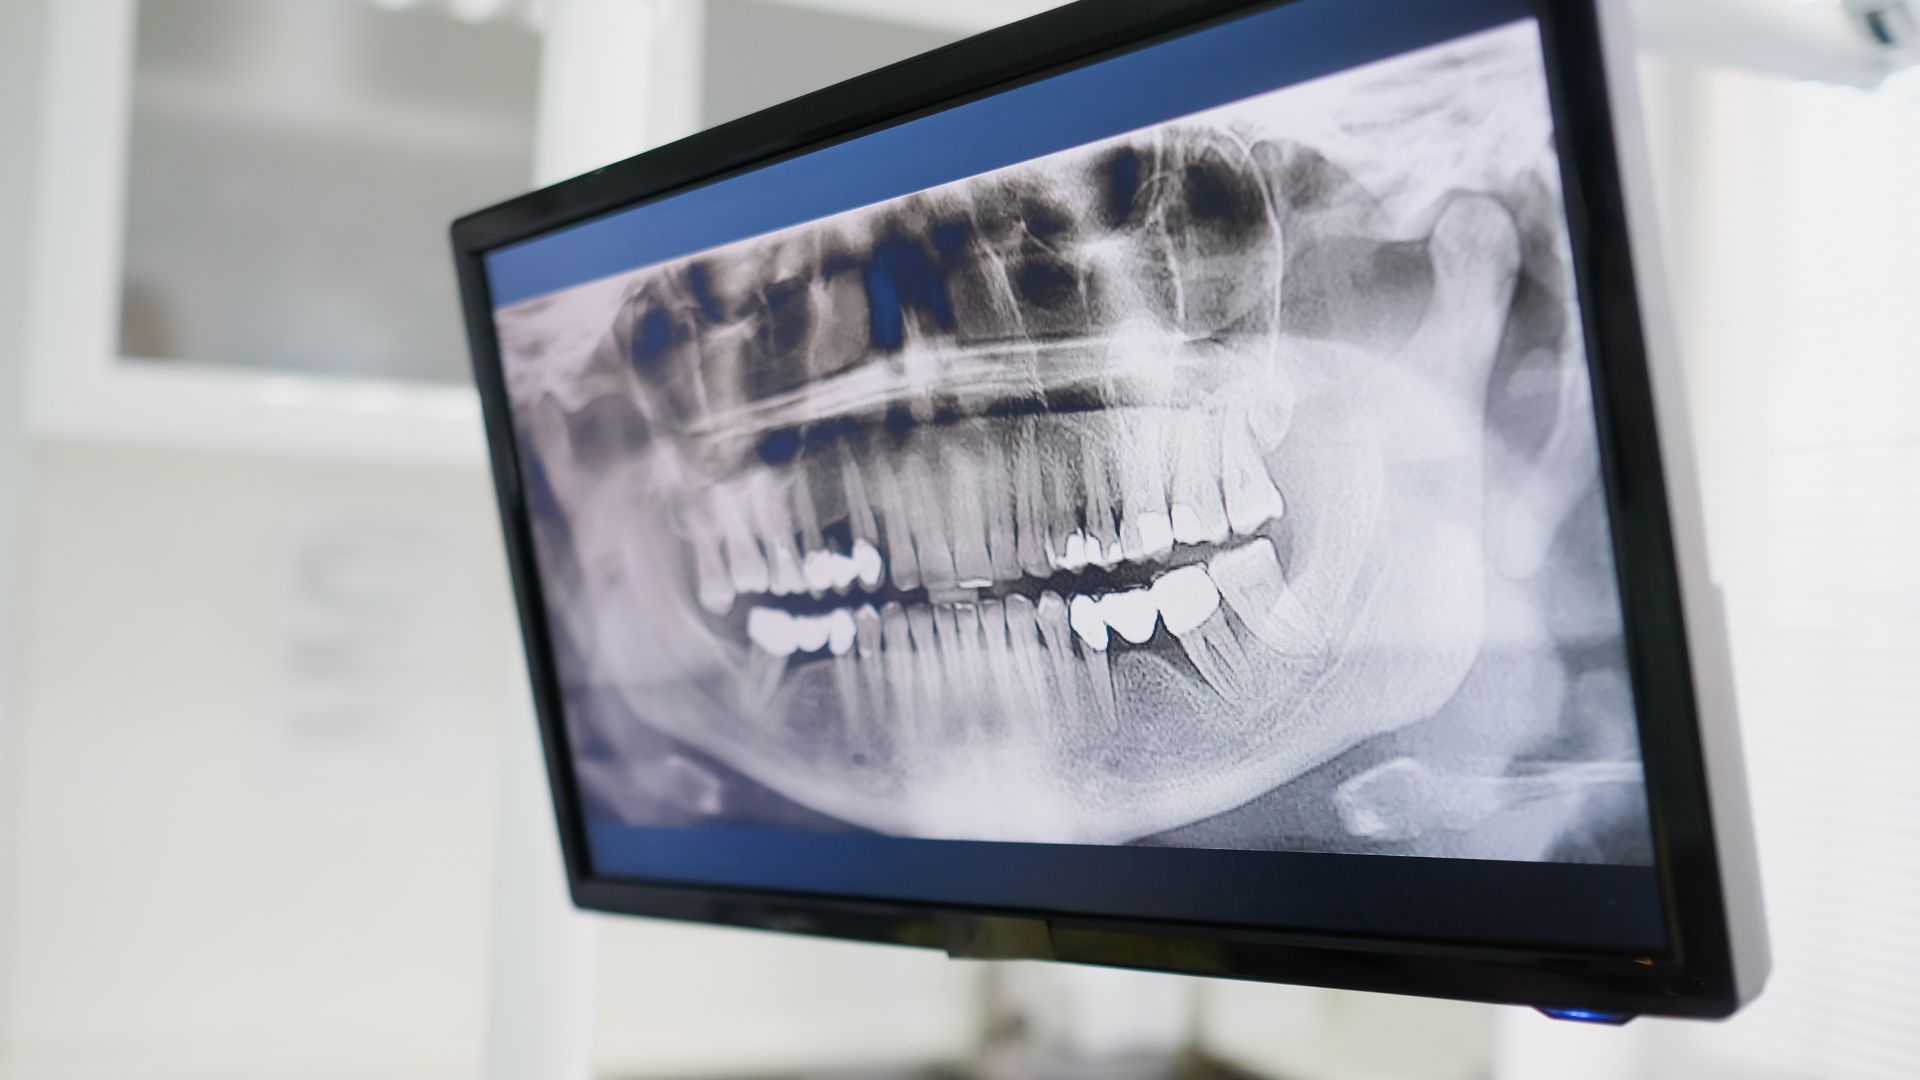

- Chụp X-quang: Họ sẽ dùng máy chụp X-quang để xem hình ảnh bên trong hàm, phát hiện răng ẩn, xương lệch, hoặc vấn đề phát triển. Có loại chụp 3D (CBCT) cho hình ảnh chi tiết hơn.